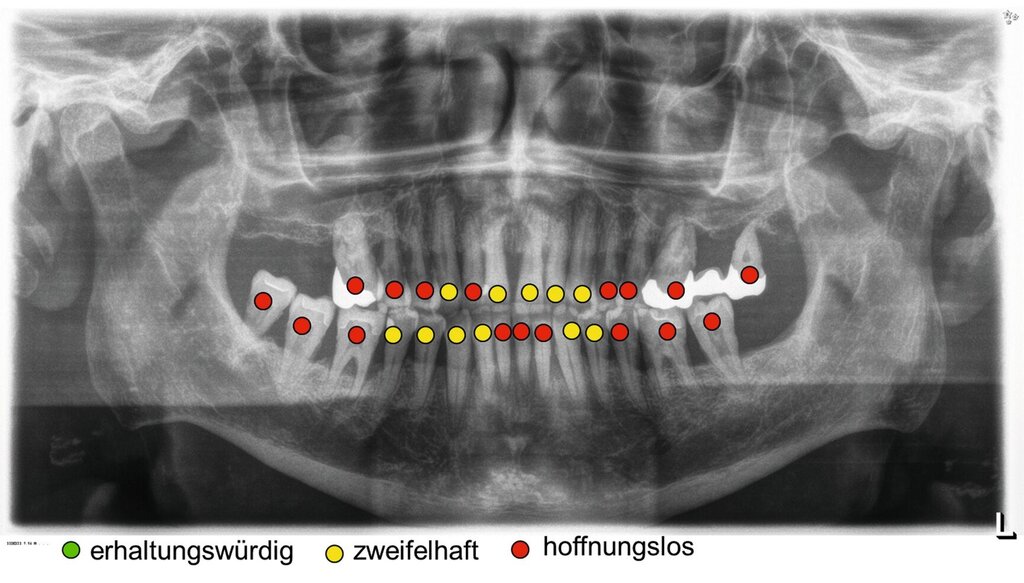

Dennoch geben Prognosesysteme, insbesondere bei komplexen Situationen, eine Hilfestellung bei der Entscheidung über den Zahnerhalt. Jedoch sollte man diese zu unterschiedlichen Zeitpunkten innerhalb der Parodontitistherapie erneut durchführen und sich wiederholt die Frage stellen, ob durch die derzeitige Therapie eine parodontale Stabilität des Zahnes erreicht werden kann [Kwok und Caton, 2007]. Die Abbildungen 5 bis 8 stellen diese Situation bei einem 56-jährigen Patienten mit Parodontitis dar, bei dem sich die zahnbezogenen Prognosen nach drei Jahren Parodontitistherapie deutlich verbessert haben.